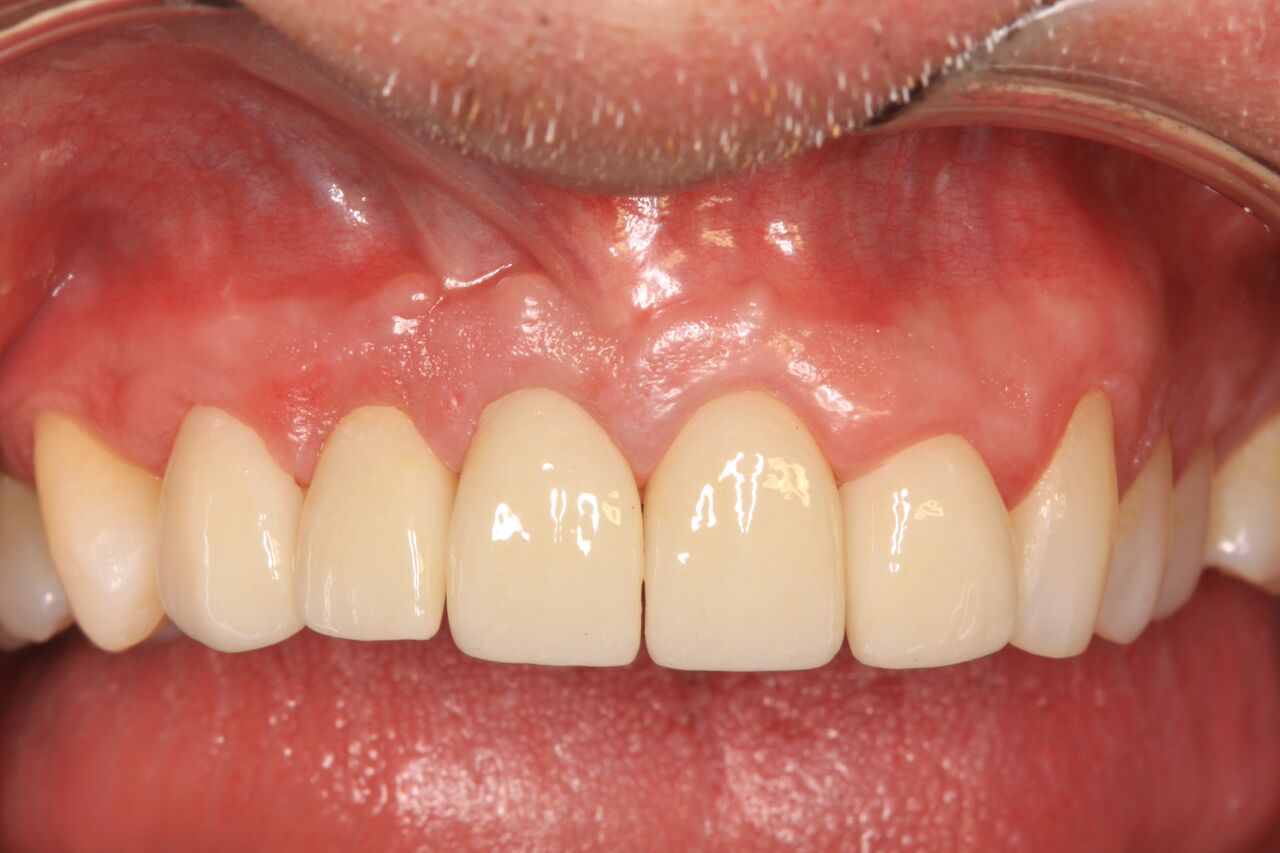

(23.) Soft tissue maturation at integration confirmation at 6 months.

Figure 23

A 42-year-old man presented with a very loose bridge on Nos. 6 through 9 with periodontally compromised retainers on Nos. 6 and 9 (Figure 17 through Figure 19), and endodontically involved No. 10 with a calcified canal. Teeth Nos. 6, 9, and 10 were extracted, the sockets fully debrided, and pontic soft tissue on Nos. 7 and 8 sculpted to be symmetrical in soft tissue contour with the contralateral lateral incisor and central incisor locations. Implants were secured in position Nos. 6 through 10 (Figure 20) in excess of 45 Ncm, the bone was milled to provide unimpeded seating of temporary abutments, and temporary crowns were fabricated chairside and adjusted to be out of occlusion in centric relation and all excursions. The temporary crowns were cemented after extrusion of excess cement extraorally and the patient was prescribed antibiotics, analgesics, and instructed in postoperative care particular to immediately provisionally restored implants. At 6 months, integration was confirmed (Figure 20 through Figure 23) and after placement of scanning abutments, the implants and soft tissues were scanned. Final crowns were fabricated from the scanned images and were cemented after extrusion of excess cement extraorally (Figure 24 through Figure 26), and oral hygiene procedures were reviewed.

(22.) Temporary crowns on Nos. 6 through 10 at integration confirmation.

Figure 22